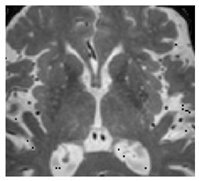

| Lacune: | CSF-filled cavity within the basal ganglia or white matter that is presumed to arise from prior small deep brain infarction [32] | ![]() | 3–15 mm Best distinguished on FLAIR with hypointense centre and hyperintense rim Hyperintense: T2 Hypointense: T1, DWI Isointense: DWI, T2*-GRE |